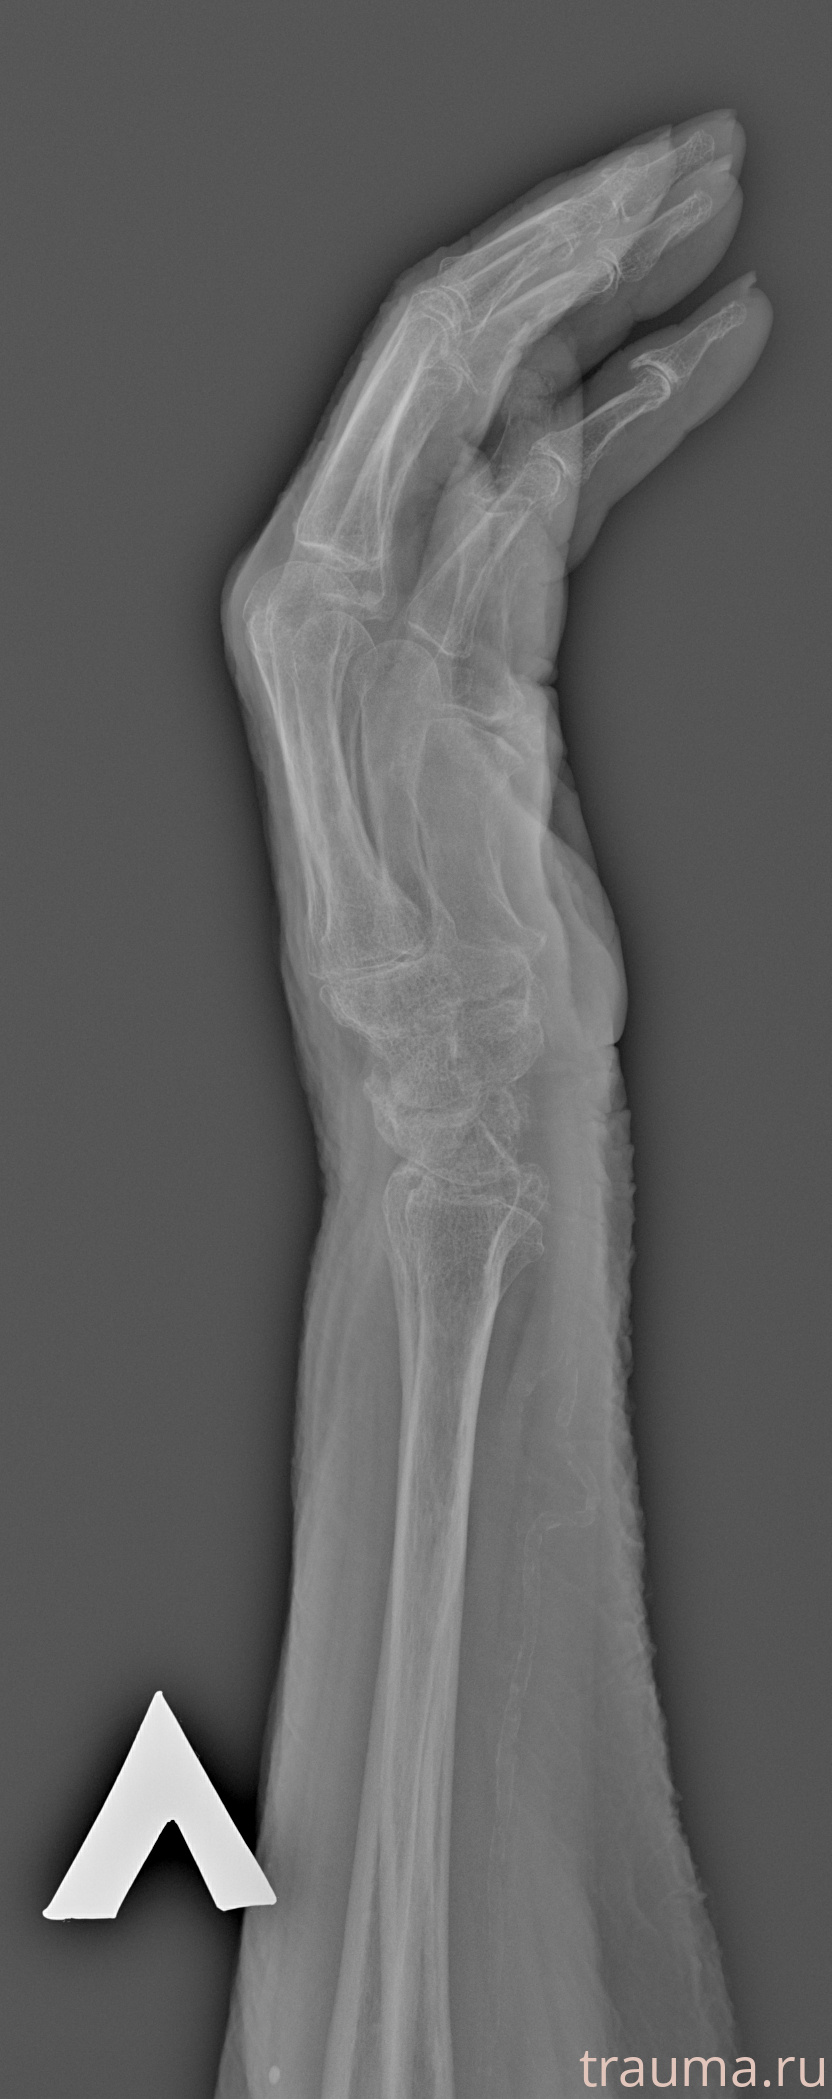

Рентгенограммы

Рентген на дому: по вашему адресу приезжает врач-рентгенолог, травматолог-ортопед с мобильным рентгеновским аппаратом, проводит диагностику травмы или заболевания, делает необходимые рентгенограммы, дает рекомендации по дальнейшему лечению. Получить качественные снимки в домашних условиях возможно благодаря уникальной методике, разработанной МосРентген Центром для института  Склифосовского